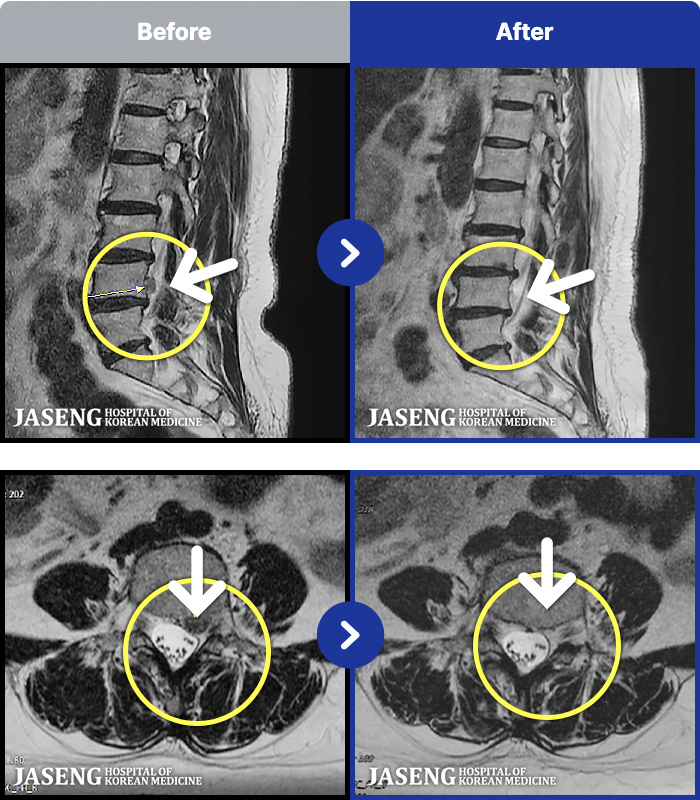

63 MRI ũ ʸ Ȯϼ.

ȯںп Ǹ ǿ ԿǾ, ο ġ ۿ Ƿ ġḦ Ͻñ ٶϴ.